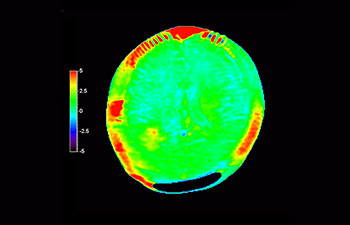

Imagerie cérébrale pour la récurrence du glioblastome

avec 3D APT